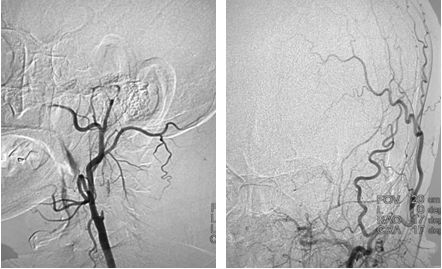

在路径途指导下,将微导丝(Transcend)、微导管(Rebar 027)沿导引导管送至左侧大脑中动脉M2段,撤出微导丝,经微导管造影,造影证实微导管位于真腔内,大脑中动脉远端血管通畅,将取栓支架Solitaire AB (6x30mm) 送至血栓处,释放取栓支架,静置5分钟后取出支架,可见支架内大量血栓,复查造影提示左侧大脑前动脉、左侧大脑中动下干通畅,左侧前大脑前动脉可向左侧大脑中动脉代偿供血,(图7)此时患者右侧肢体无力症状明显好转,仍有不完全混合性失语,观察10分钟后复查造影提示血流仍然通畅,颈动脉支架处血流通畅,遂结束手术,继予以替罗非班抗栓治疗。

图7